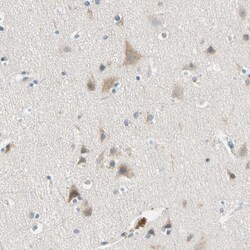

Immunogen sequence: FQSNRMDDQR CCLQEKNCHT ASTTTSSTPP KMMLKTSSVP VVSPNTDEFL DLLASSQSRR LDDQRASFSN LPGLRLTQNS QSVLSHLMTN DNKEADEDFF D Highest antigen sequence identity to the following orthologs: Mouse - 78%, Rat - 75%.

The protein encoded by this gene belongs to a family of proteins that modulate activation of G proteins, which transduce extracellular signals received by cell surface receptors into integrated cellular responses. The N-terminal half of this protein contains 10 copies of leu-gly-asn repeat, and the C-terminal half contains 4 GoLoco motifs, which are involved in guanine nucleotide exchange. This protein may play a role in neuroblast division and in the development of normal hearing. Mutations in this gene are associated with autosomal recessive nonsyndromic deafness.

| Applications | Immunohistochemistry (Paraffin), Western Blot |